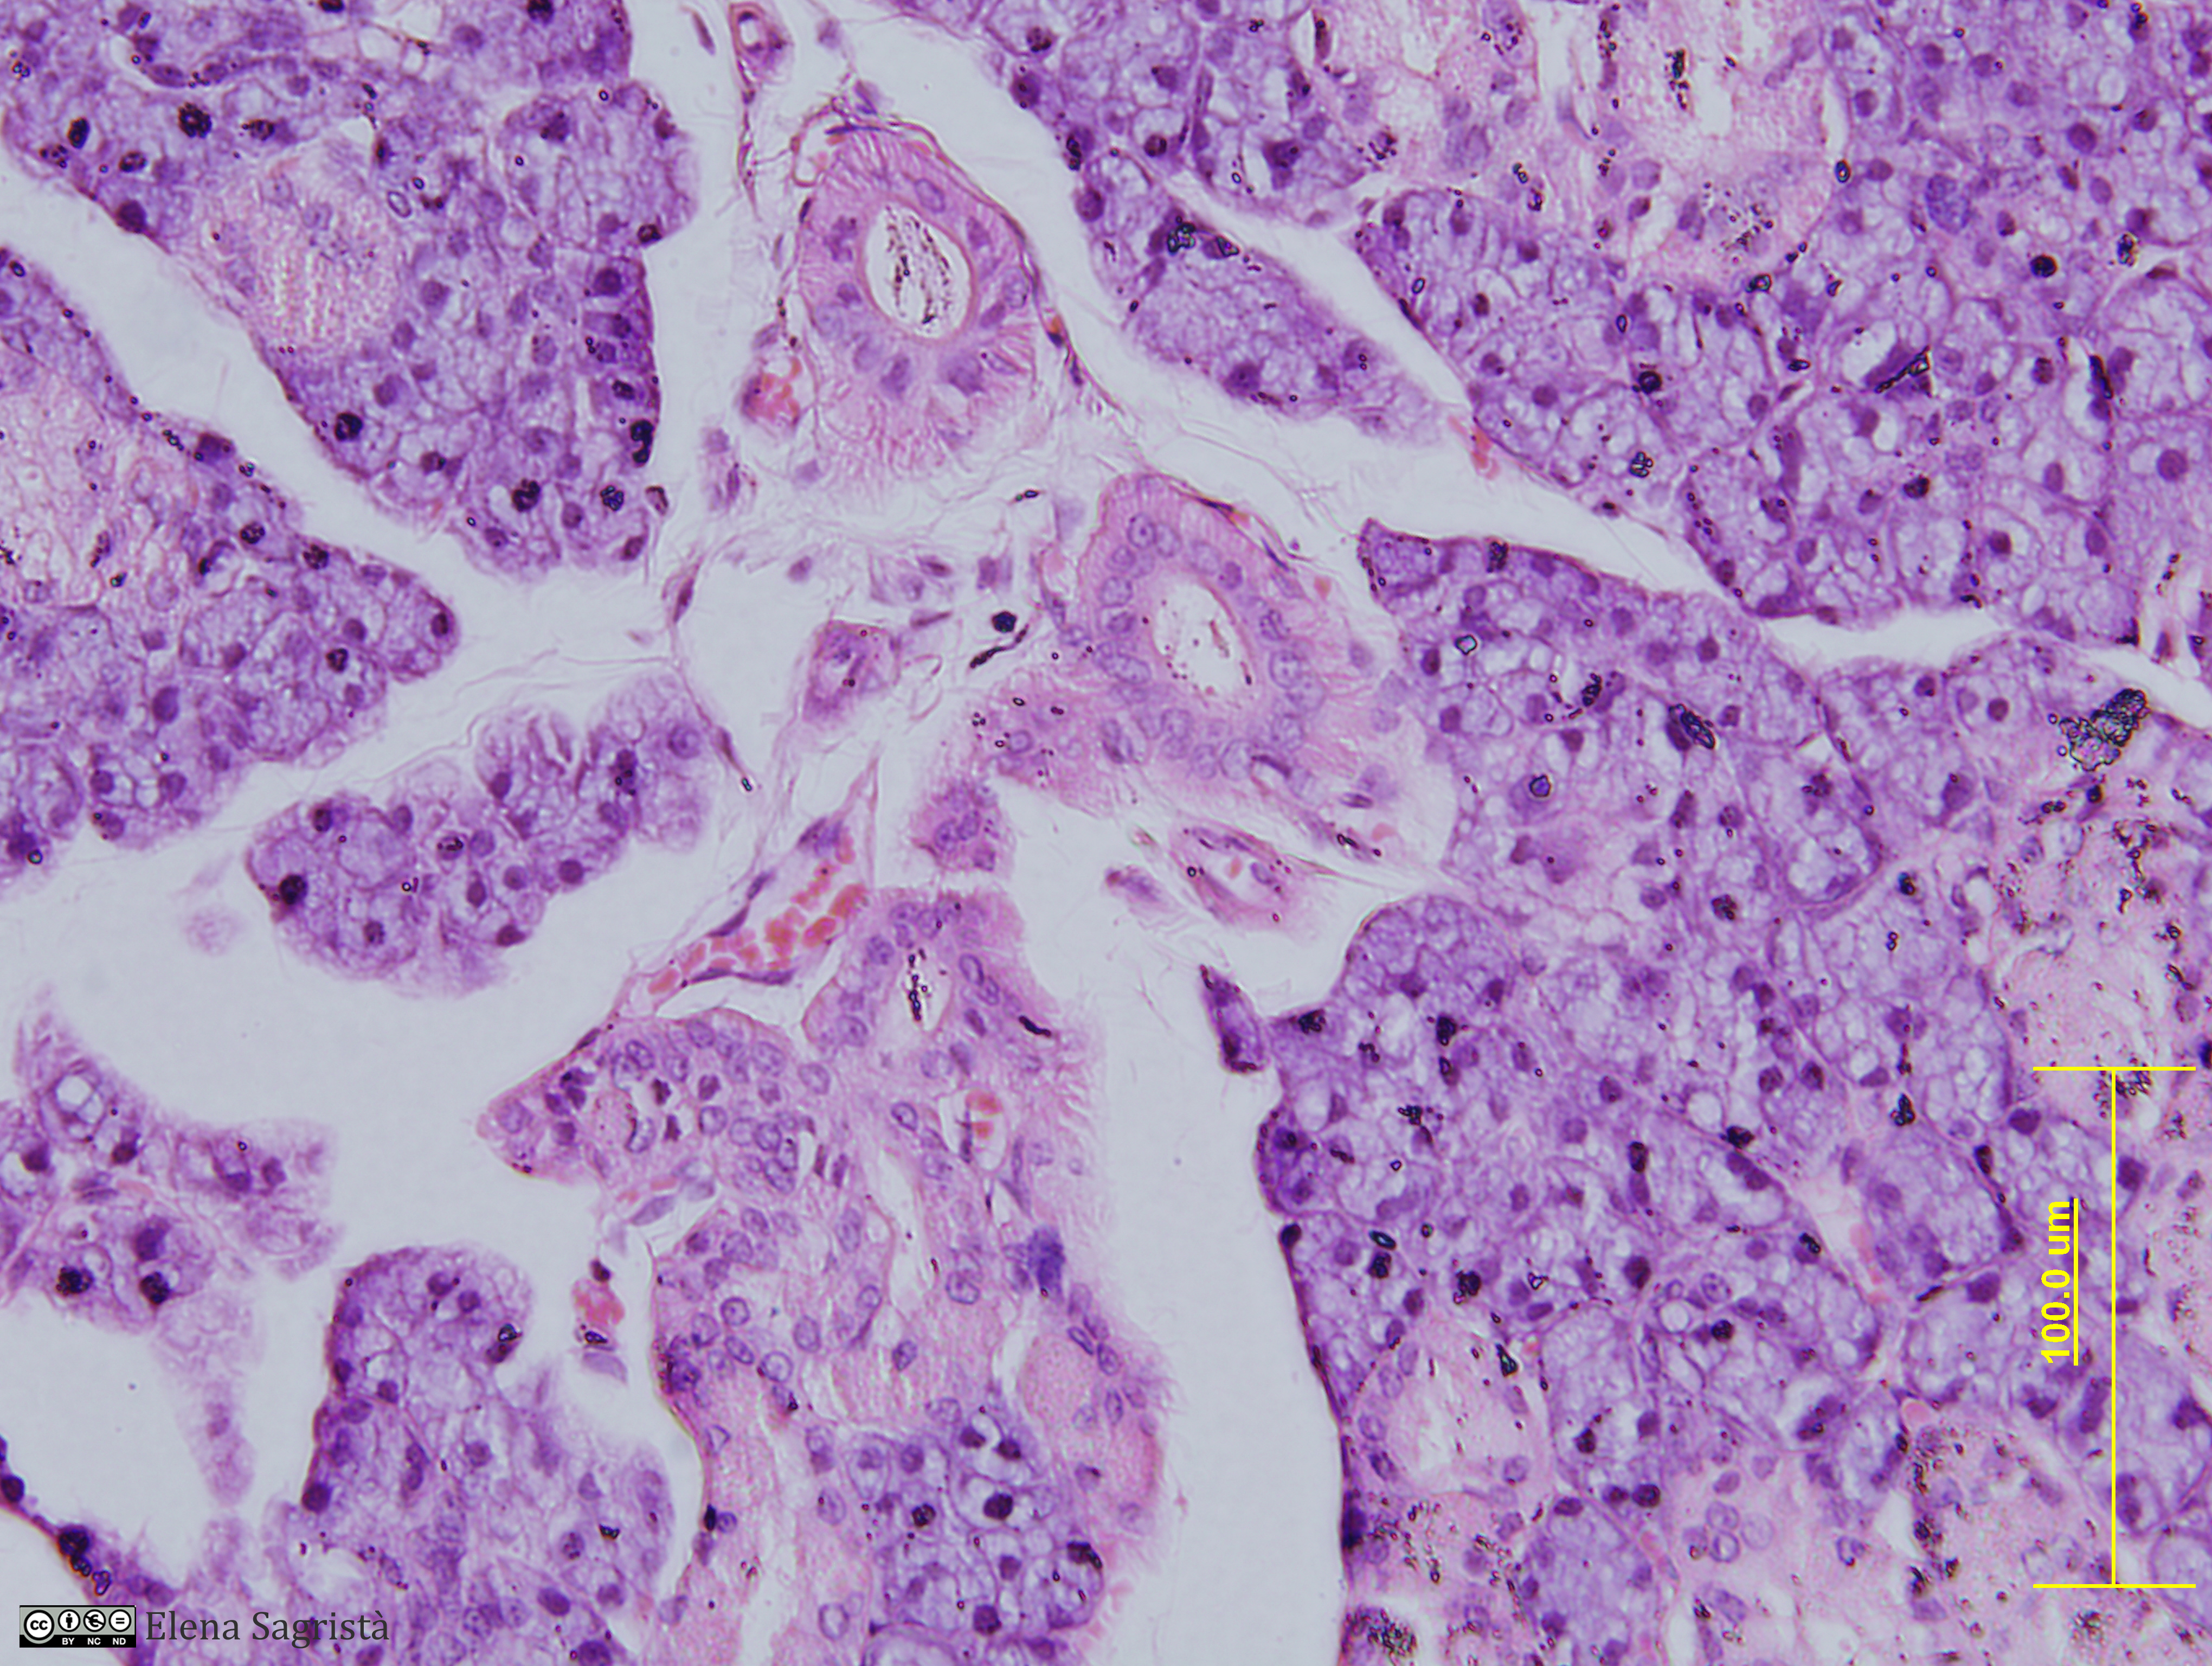

Histologia imatges: 14 Llengua

Imatges de preparacions histològiques de Llengua. Microscopia òptica.